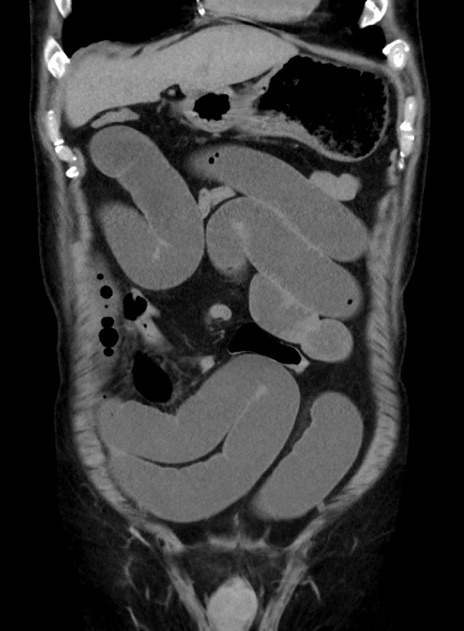

横断像

【症例】70歳代 男性

【主訴】腹痛・嘔吐

【現病歴】昨晩より、嘔吐・腹痛あり。今朝になっても嘔吐あり。来院。

【既往歴】心臓バイパス手術、開腹胆摘、腸閉塞

【身体所見】BP 107/71mmHg、HR 116/min、腹部:平坦、軟、下腹部に軽度圧痛あり。反跳痛なし。

【データ】WBC 15100、CRP 0.32